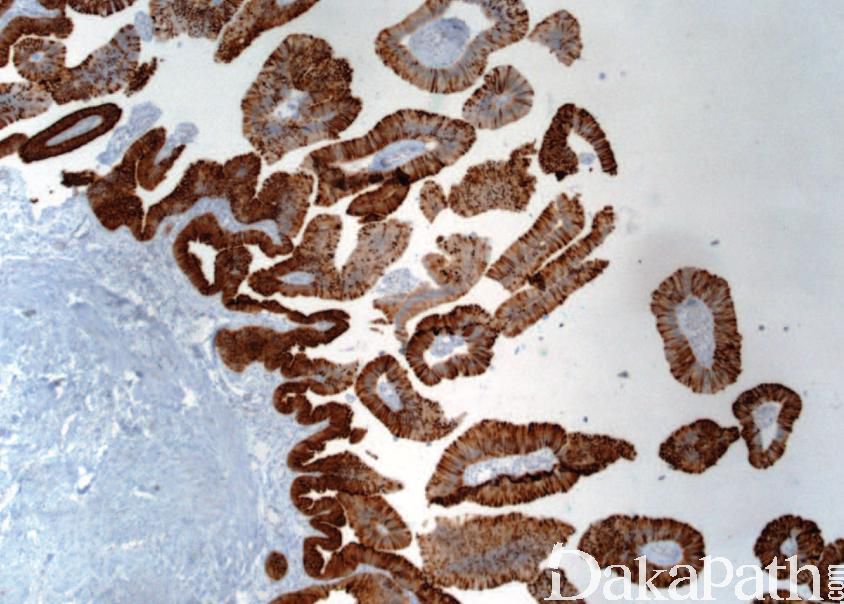

免疫组织化学染色:

CK20. CK7. CDX2 常阳性。EMA、GATA3. PSA 阴性。偶尔可异常表达 P501s 和 PSMA。